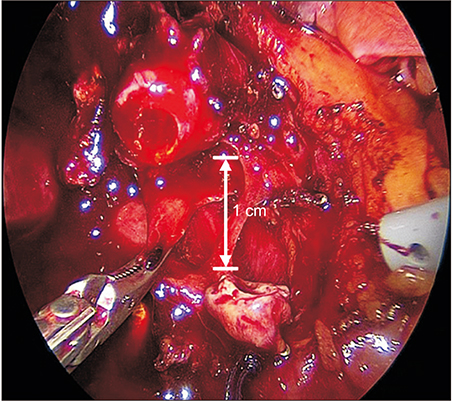

This report describes the laparoscopic end-to-end biliary reconstruction with T-tube for transected bile duct injury (BDI) during laparoscopic cholecystectomy.

Between January 2014 and December 2017, 2,901 patients underwent laparoscopic cholecystectomy at a single institution. Among them, 8 patients experienced a transected BDI during laparoscopic cholecystectomy, so the surgeon performed laparoscopic end-to-end biliary reconstruction with T-tube. Our patient series consisted of 6 women (75%) and 2 men (25%) with a mean age of 48.3 years (median, 49 years; range, 29-77 years). Two cases were converted to open surgery. The most common injured site was the common bile duct (5 of 8, 62.5%). The most common injury type, using Bismuth's classification system, was type I (3 of 8, 37.5%). The mean operating time was 136.8 minutes (median, 135.0 minutes; range, 0-180.0 minutes). The mean hospital stay was 7.0 days (median, 4.5 days, range: 3.0-21.0 days). The mean follow-up was 36.4 months (median, 34.0 months; range, 16.0-63.0 months). We observed one postoperative complication during the follow-up period. The patient had an anastomosis site leakage and was cured after reoperation.

Laparoscopic end-to-end biliary reconstruction with T-tube for transected BDI during laparoscopic cholecystectomy seems to be safe and feasible in selected patients. However, long-term follow-up to identify complications from bile duct stricture remains important.